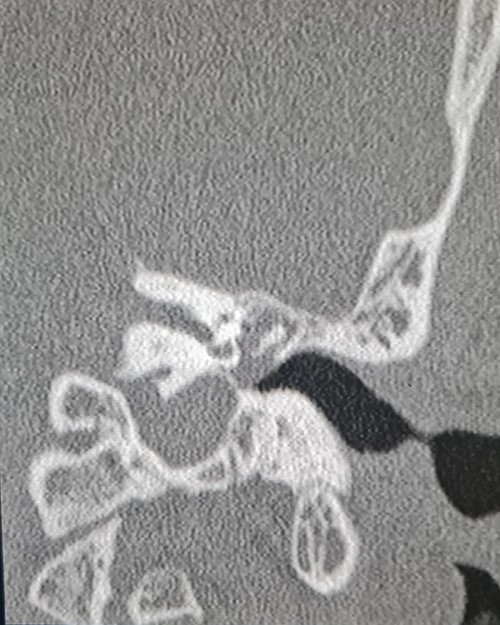

A 35-year-old male with no medical history, presented to us with gradual left ear hearing loss and ear fullness over 1-year duration. There was no prior history of trauma or exposure to unusually loud noise and no notion of family deafness. A physical examination showed a normal left external auditory canal and the tympanic membrane was bulging and thickened. Audiometry objectified conductive moderate hearing loss. A contrast-enhanced computed tomography scan was performed revealing a mass with soft tissue density. The mass localized into the middle ear with extent to the attic, pushing and dislocating the ossicles, without evidence of bone invasion (Fig. 1).

Coronal computed tomography image showing the mass with soft tissue density filling the middle ear cavity.

On the computed tomography, the tumor is characterized by soft tissue density in the mastoid bone without blood vessels, which can be extended to the middle ear and mastoid. The ossicular chain is usually embedded into the tumor, but there is no bone erosion [2].